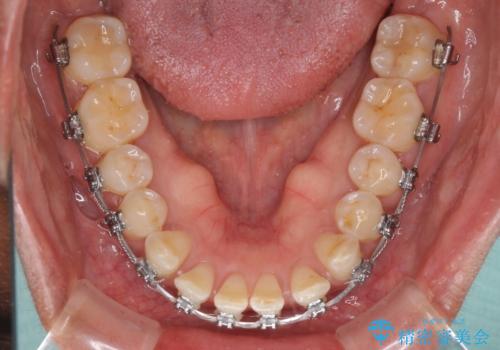

反対咬合の改善 途中で出産をしながらワイヤー矯正

- 矯正装置

- メタルブラケット

- 前歯の隙間と反対咬合を気にして来院された患者様です。

マウスピース矯正も提案しましたが、しっかりと使用する自信がないとのことで、ワイヤー装置により矯正治療を行うこととしました。

咬合力が強く、反対咬合の改善に時間がかかりましたが、その後はスムーズに進めることができました。

途中、妊娠と出産があり、治療が中断したため、治療期間は延びましたが、出産も矯正治療も無事に終えることができました。